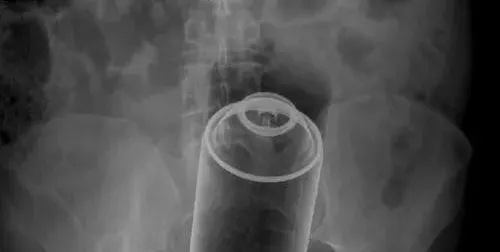

По спешност в „Пирогов“, със заврян дезодорант в задните части, се оказа 14-годишен младеж. Историята на малкия палавник се разиграла в началото на месеца, когато бил закаран в спешното отделение на „Пирогов“ от родителя си.

Човекът не само треперел от нерви, а и умирал от срам. Затова накарал наследника си да разкаже на дежурната лекарка какви ги е вършил в собствената си стая. Хлапакът дълго време мълчал, но притеснен от случката, споделил, че си е пъхал многократно дезодорант в задните части. Обаче станала беля – флакончето, което предварително било намазано с гел, потънало дълбоко навътре.

Преди време негова позната го помолила да направи това пред камера, за да й докаже, че истински я обича. Тийнейджърът нямал много желание, ама започнал да го прави, за да получава одобрение по мобилния телефон. Лекарите в „Пирогов спасили положението с операция.